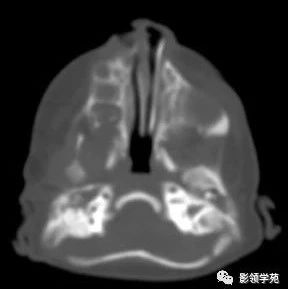

胎儿异常外脑——露脑畸形 影领学苑 · 公众号 · · 5 年前 · |